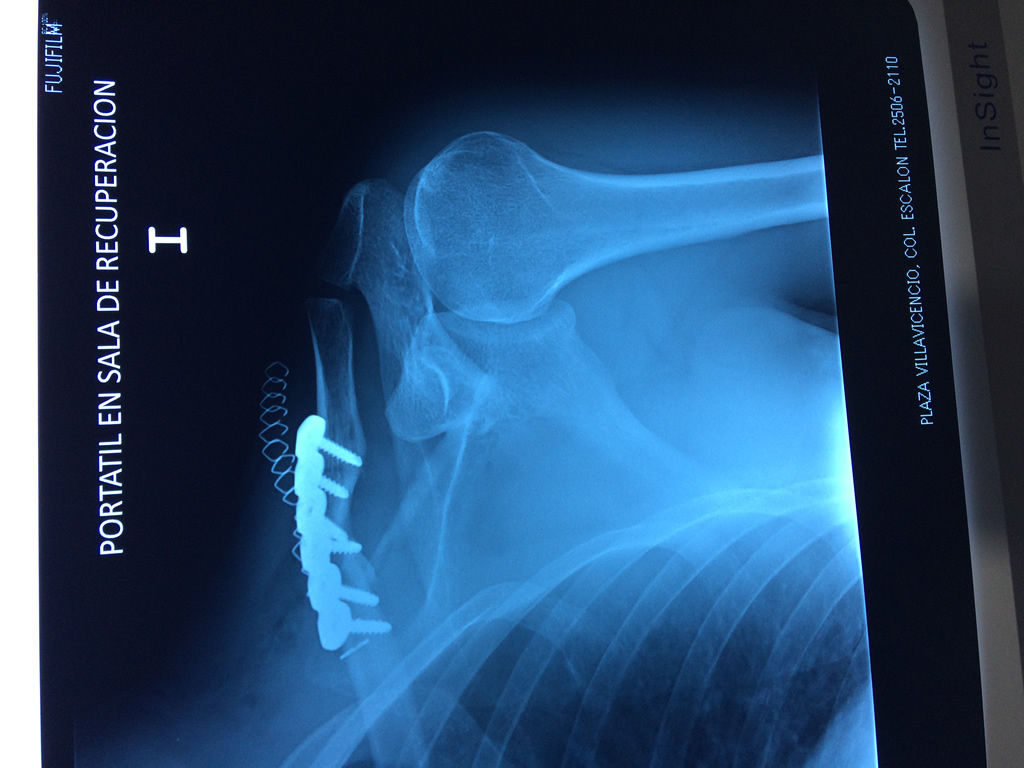

Cirugías de Calcaneo - Clavícula

La clavícula es un hueso largo, con forma de "S" itálica, situado en la parte anterosuperior del tórax. Junto con la escápula forman la cintura escapular. Se puede palpar por toda su longitud y se extiende del esternón al acromion de la escápula, siguiendo una dirección oblicua lateral y posterior.